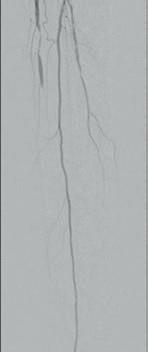

Figure 1: Diffuse calcified occlusive disease on pre-procedural arteriogram

a) Anterior tibial (AT) artery b) Dorsalis pedis (DP) artery

Figure 2: Shockwave Javelin in therapy a) In the AT b) In the DP

Figure

3: Definitive therapy, AT and DP treated with a 2.5x150mm angioplasty balloon a) Completion angiogram of AT b) Completion angiogram of DP